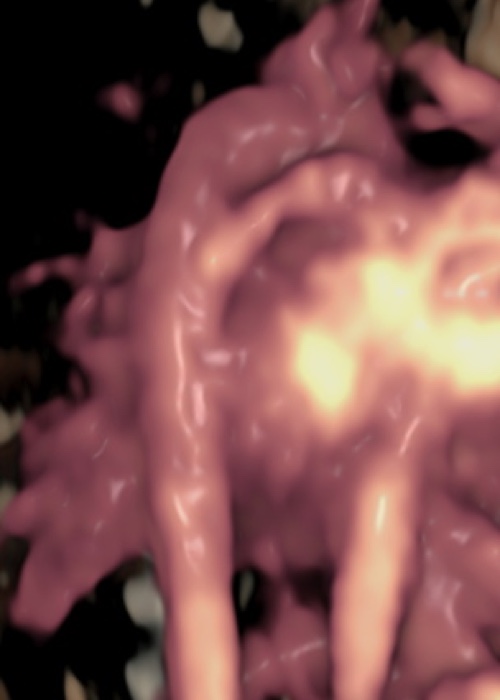

Ecocardiografia fetale